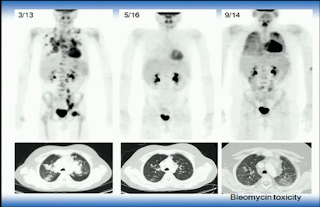

호지킨스 bleomycin lung toxicity